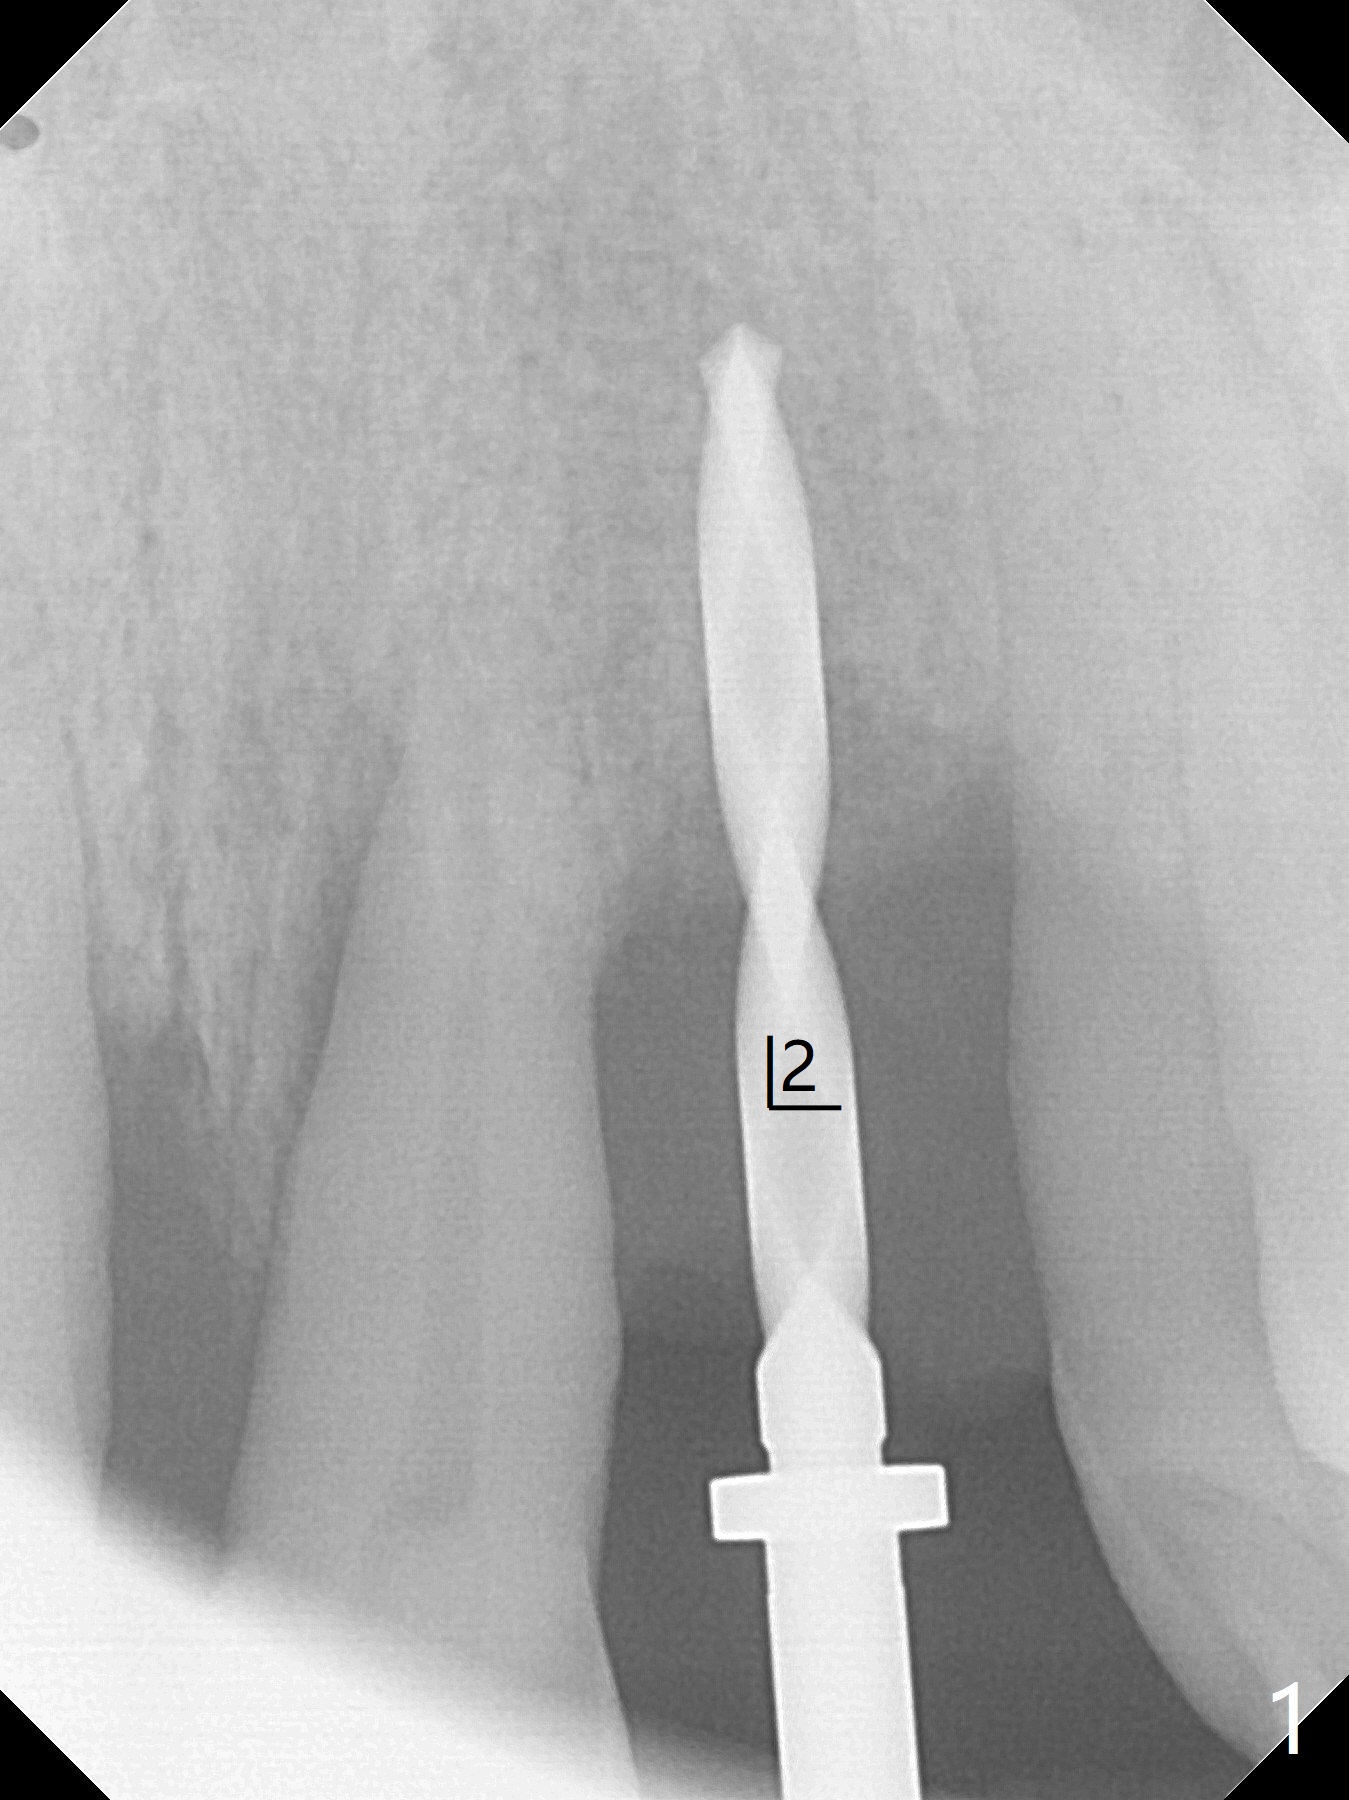

实验结果表明红管抽取上清液形成粘性骨块比白管快。左上二拔除,即刻徒手钻洞(图一),初步植入3.8x11.5毫米植体(图二),调整植体深度,然后放置直径4.5毫米长基台(图三,DIO UF; 牙龈厚度大于6毫米),最后填入大量粘性骨粉(图四,五 *),植体颊侧近中骨粉不足(图五 ^),之后再次充填骨粉。制作即刻修复物,颊侧瘘道和牙槽窝开口放置PRF膜。术后三周临时牙冠松动,取出后者,颊侧空间有两个区域:牙龈和骨粉(图六:白,黑星号)。由于脑部手术,术后接近一年病人回来取模。由于基台长,临时牙冠还没有脱落(图八)。牙龈袖正常(图九:*)。术后一年骨粉仍在植体,基台交界处(图十)。